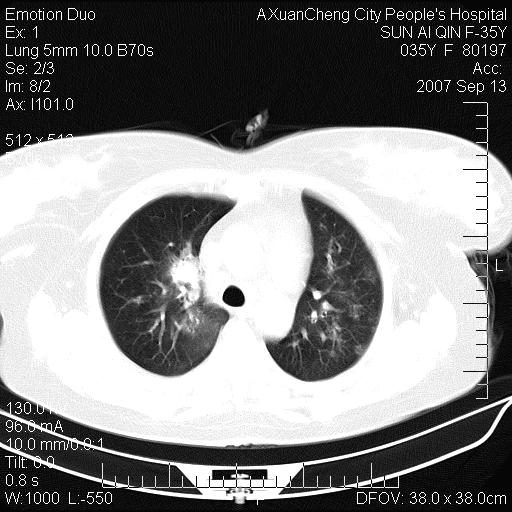

以下是引用天南地北在2007-9-13 13:43:00的发言:[br]考虑双肺、肺门侵润

以下是引用ydx_74在2007-9-13 15:42:00的发言:[br]仅看片,考虑右上肺癌并双肺转移,结合病史,考虑肺门、肺内淋巴侵润

以下是引用同在2007-9-13 15:08:00的发言:[br]支持肺门及双肺侵润.